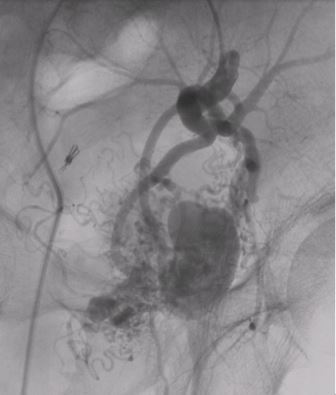

肝腫瘍に対する肝動脈化学塞栓術

- 腹腔動脈造影。腫瘍濃染がみられる。